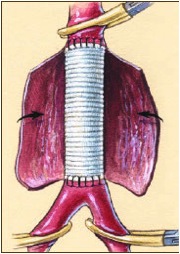

O tratamento convencional do aneurisma de aorta é a substituição do segmento dilatado por um “tubo” sintético. A cirurgia é feita com anestesia geral e incisão no abdome ou no tórax. A cirurgia de correção dos aneurismas de aorta já é feita há mais de 40 anos sendo um método consagrado pela sua eficácia e segurança comprovado ao longo dos anos. Quando executado por cirurgiões experientes, em ambiente apropriado após preparo adequado do paciente, apresenta pequenas taxas de complicações.

O tratamento endovascular consiste no implante de um tubo sintético moldado numa estrutura metálica (endoprótese) por dentro dos vasos sanguíneos permitindo, desta forma, a passagem do sangue por dentro do tubo, sem aumentar a pressão sobre a parte dilatada da artéria, evitando-se, assim, a sua ruptura. O procedimento pode ser feito com bloqueio epi ou intradural (anestesia peridural ou raquianestesia) combinado com sedação ou anestesia geral, dependendo de cada caso. Todo a cirurgia pode ser feita através de pequenas incisões nas virilhas ou, em casos selcionados, através de punções. Sua vantagens são: menor agressão cirúrgica (não há abertura da barriga ou do tórax), menor perda sanguínea, tempo cirúrgico menor, menos dor pós-operatória e rápida recuperação. O tempo de internação é de 2 dias e o retorno ao trabalho pode ser feito em 7 a 10 dias.

Cabe lembrar que nem todos os casos podem ou devem ser tratados por este método. Apesar das suas claras vantagens, existem casos em que a cirurgia convencional oferece resultados melhores sem comprometer a segurança.

Fato é que o tratamento endovascular dos aneurismas de aorta vem sendo empregado com maior frequência ao longo dos anos, tornando-se o método preferencial. Estatísticas estadosunidenses mostram que na década de 90 apenas 20% das correções dos aneurisma de aorta eram feitas por técnica endovascular. No início dos anos 2000, a proporção era de 50% para cada técnica. Atualmente, 80 a 90% dos pacientes são tratados por técnica endovascular.

Tratamento endovascular de aneurisma de aorta abdominal